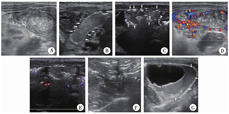

超声征象(图1)判断依据:①肠壁增厚:肠壁厚度≥2.7 mm[5]; ②肠壁变薄:肠壁厚度≤1 mm[5]; ③肠壁积气:肠壁内有点状或簇状气体强回声;④肠壁血供评估:使用线阵探头,速度量程设置为8.6 cm/s,如血流信号>9个血流信号/cm2,定义为血流信号丰富;如未探及血流信号,则将速度量程降低至2.9 cm/s,如仍未探及血流信号,则定义为血流信号消失[3]; ⑤门脉积气:门脉主干及分支管腔内点状或线状分布强回声;⑥肠管蠕动:动态观察1 min,记录肠管有无蠕动;⑦透声差的积液:腹腔积液伴有较多絮状或点状沉积物或伴有分隔。超声医师在检查过程中对NEC患儿的临床分期均不知情。

A:肠壁增厚(测量键之间); B:肠壁变薄(箭头); C:肠壁积气(箭头); D:肠壁血流信号增多;E:肠壁血流信号消失;F:门脉积气;G:透声差的积液(箭头)